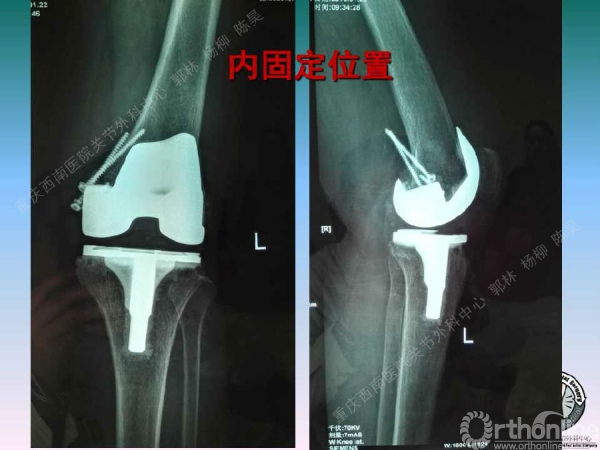

导读:文中,来自重庆西南医院的郭林教授为大家介绍了股骨冠状位关节外畸形的TKA的相关知识,并详细阐述了关节外畸形的概念、诊断、关节内滑移截骨技术等相关内容。

滑移截骨纠正关节外畸形

关节内滑移截骨的缺点和并发症